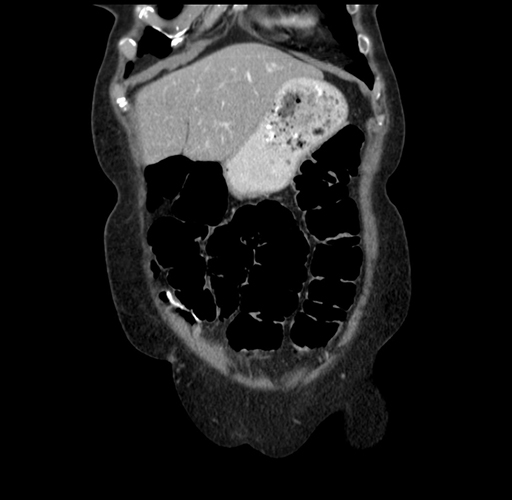

Right hemihepatectomy (to posterior sectionectomy) [case 13]

Imaging Analysis

Look through the patient's CT scan to identify any areas of concern for the necessary procedure.

Based on your CT findings, which issue(s) would give reason for "planned slowing down moment(s)" in this case?

Considering a standard right hepatectomy procedure, what step(s) of the operation would you do differently in this case?